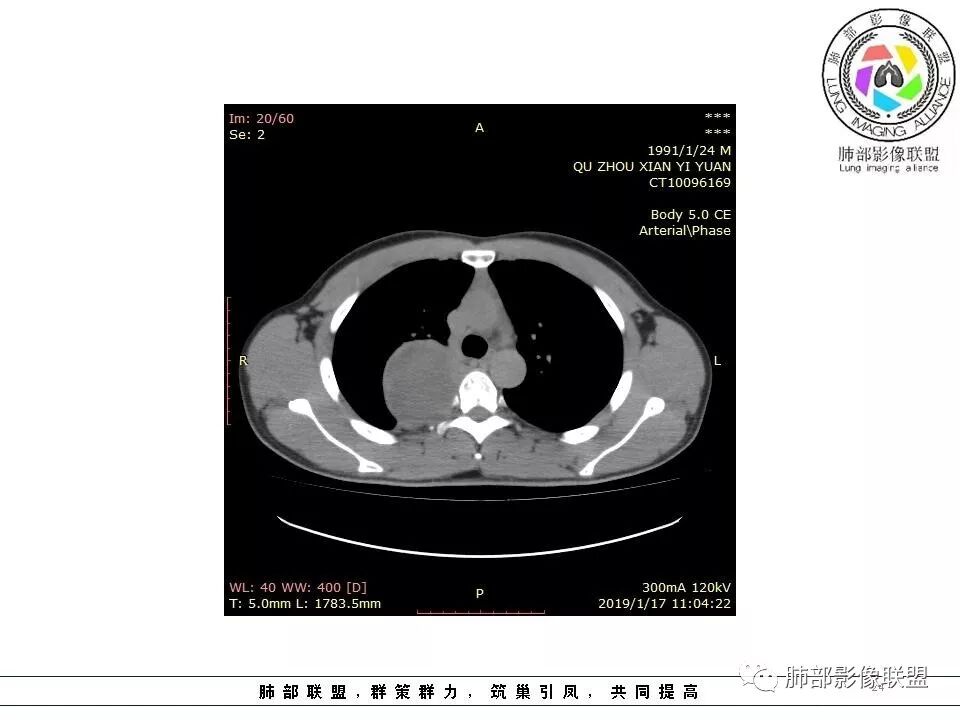

右后纵膈脊柱旁软组织占位,形态规则类圆,边缘光整,肺组织受压,胸膜尾,肋间动脉供血。中度不均匀延迟强化。

后纵隔脊柱旁占位性病变,疾病谱有神经鞘瘤,sft,节细胞瘤,髓外造血。此例有胸膜尾征,蛇纹征 ,延迟强化。考虑胸膜孤立性纤维瘤。看到有供血动脉,但不知道是哪里的血管。

后纵隔类圆形新生物,边缘光滑,胸膜尾征明显,贴近脊柱,蛇纹,血供丰富,考虑后纵隔软组织肿瘤,具体类型看不出来,鉴别神经鞘瘤。

右后纵膈脊柱旁软组织占位,边界清晰,光整,肺组织受压。胸膜被掀起,肋间动脉供血,中度不均匀延迟强化。考虑神经鞘瘤,不除外纤维瘤

右后纵膈脊柱旁软组织影,与纵隔结构分界不清,形态规则类圆,边缘光整,肺组织受压,胸膜尾,肋间动脉供血。肺动脉推移,中度不均匀延迟强化。考虑神经来源,神经鞘瘤,神经纤维瘤二者不易鉴别。

青年男性,间断胸痛;右侧脊柱旁可见一类圆形软组织密度影,密度欠均匀,增强扫描呈轻中度持续强化,邻近肺组织及肺动脉推移,可见肋间动脉供血,部分胸膜下脂肪可见,部分层面似见与右侧椎间孔相连。考虑后纵隔神经源性肿瘤。

后纵隔脊柱旁占位性病变,有胸膜尾征,胸膜下脂肪可见,蛇纹征,明显强化。考虑孤立性纤维瘤。

定位肺外。强化不均匀,散在血管。考虑sft,鉴别:神经鞘瘤,付节瘤,cd。鞘瘤有ab区,付节瘤高血压,cd强化,形态不支持。

病灶定位脏层胸膜,肺组织受挤压,有胸膜尾征,动脉期可见血管支配,考虑肺动脉供血,静脉期,强化增强明显,符合快进慢出特点,病灶内可见低密度区,考虑胸膜孤立纤维瘤。

右侧后纵隔脊柱旁占位,边缘光滑清晰,内侧肺组织受压,外侧可见胸膜尾征,增强持续强化,并可见蛇纹血管征。考虑SFT

青年男性,间断胸痛。右后纵膈脊柱旁软组织占位,形态规则类圆,边缘光整,肺组织受压,D字征,胸膜尾,肋间动脉供血。中度不均匀延迟强化。无支气管进入考虑来源于肺外、肿块与脊柱间未见明显脂肪间隙,考虑来源于胸膜外,考虑神经源性肿瘤,建议穿刺活检。